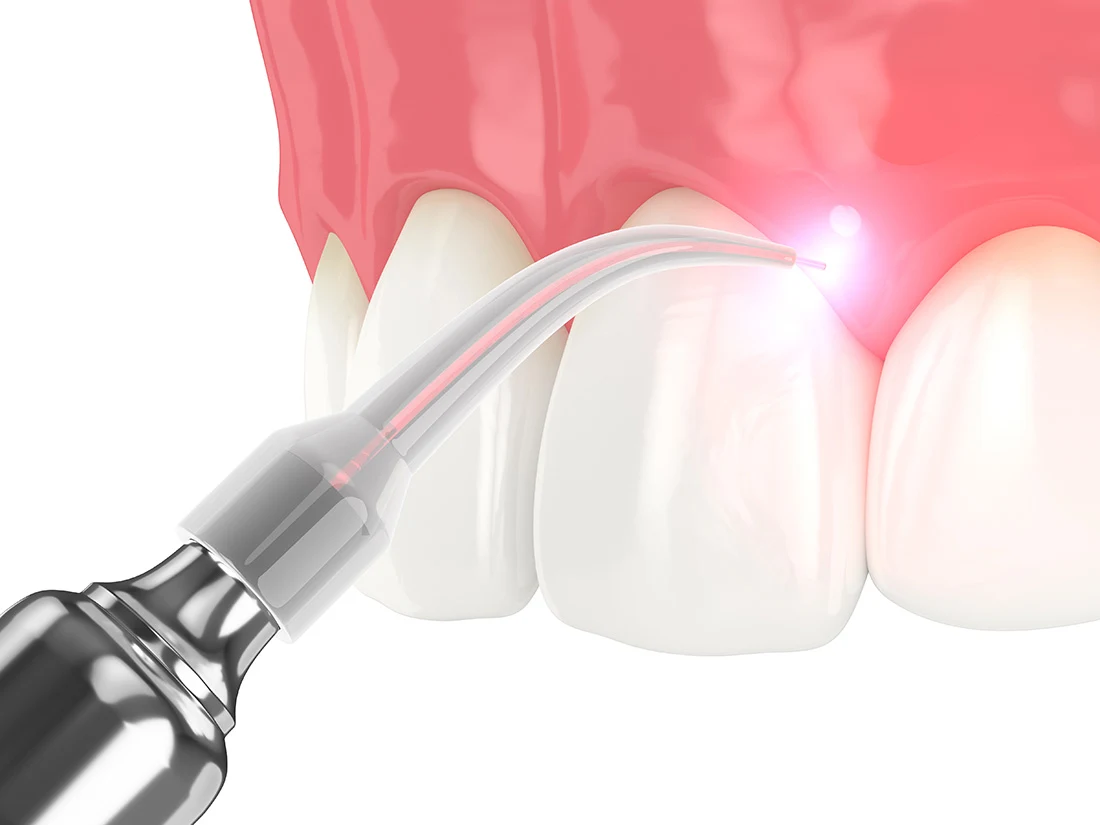

Soft-Tissue Laser Therapy

While the thought of oral surgery and periodontal care may seem daunting, laser dentistry has revolutionized the way in which these procedures are performed. Our soft-tissue laser utilizes a highly-focused beam of light to perform a wide variety of treatments and can be used in place of more invasive methods for more comfort and faster recoveries. Get in touch with us today to find out laser dentistry can benefit you!